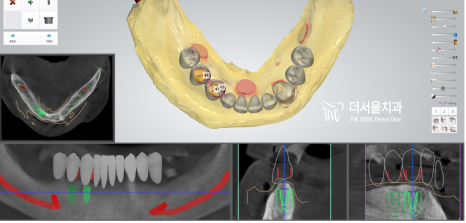

컴퓨터 분석을 통해 식립 위치를 정한 뒤

본격적인 치료 과정에 들어갔습니다.

보험 적용이 가능한 임플란트는

PFM 크라운으로 만들어진 것인데요.

해당 보철을 통해 틀니를 유지, 지지할 수 있는

지대치를 만들어 주었습니다.